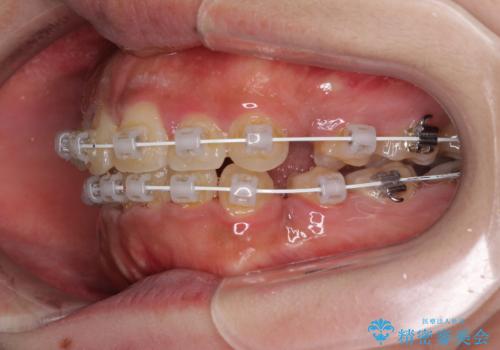

- 審美装置

- 口元の突出感と上下前歯のでこぼこを気にして来院された患者様です。

上下前歯部叢生のスペース獲得のため、上下顎左右小臼歯各1歯(計4本)を抜歯して、矯正治療を行うこととしました。

口腔内の清掃性に問題があり、虫歯のリスクが極めて高かったため、短期で治療を終えることを最優先に治療を進めました。